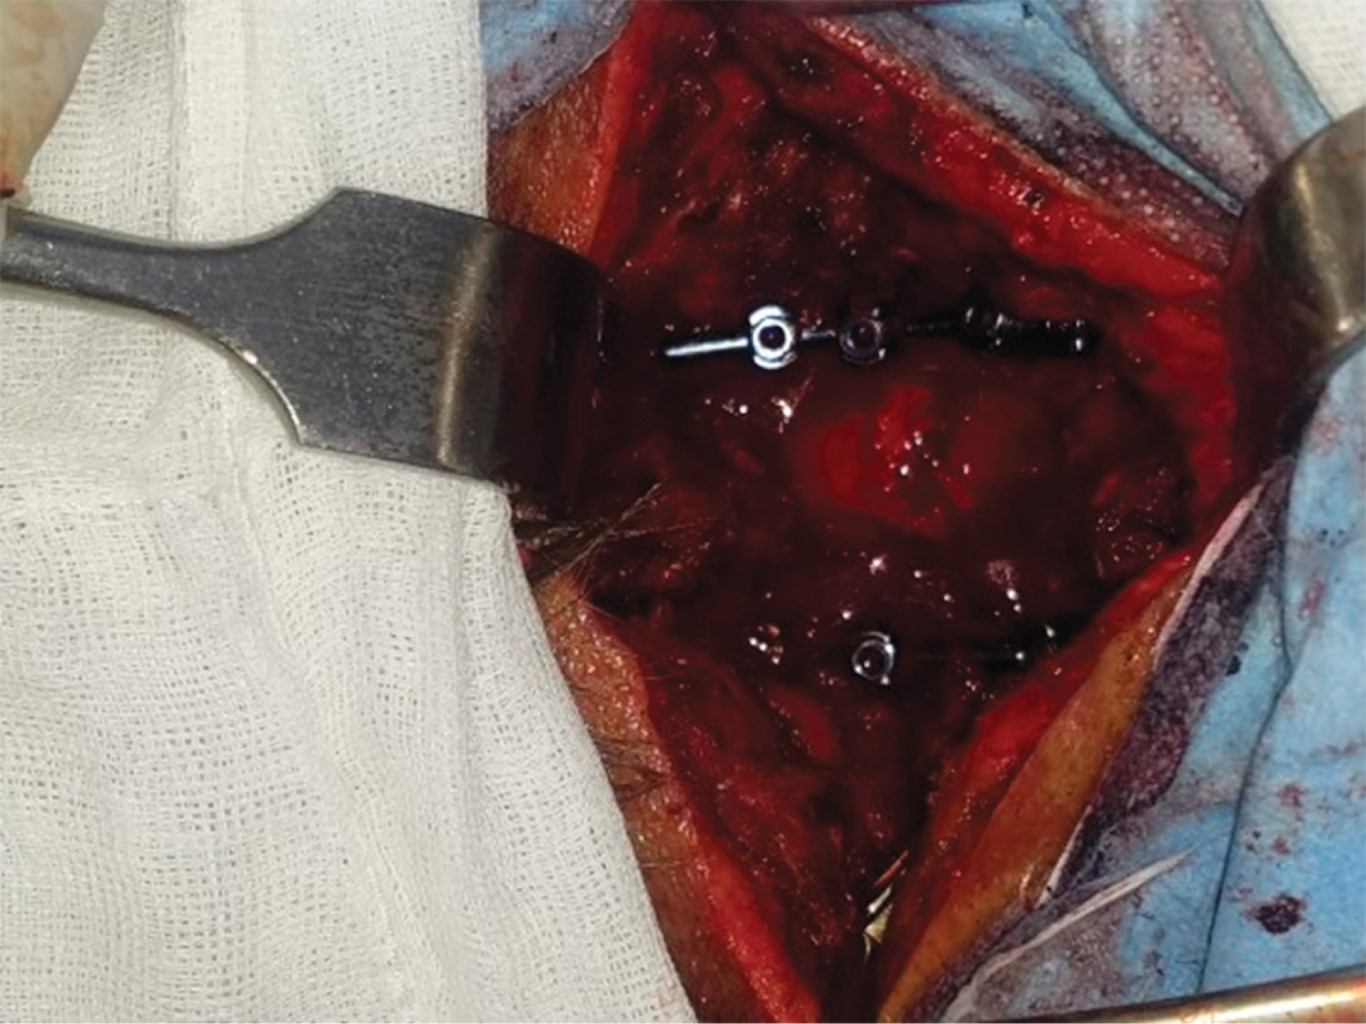

Diffuse idiopathic idiopathic skeletal hyperostosis (DISH), or Forestier's disease is a rare disease of unknown etiology. It is a systemic condition in which ossification of the anterolateral sides of at least four contiguous bodies, calcification of ligaments and entheses develops and is accompanied by spinal pain predominantly in the thoracic spine. In this case report we present a 70-year-old female patient presenting with DISH with complete spinal cord injury from c7 to distal on ASIA A scale following a fall from her own plane of support managed surgically with posterior cervical approach and instrumentation of lateral masses and decompression with good clinical evolution and partial clinical recovery to ASIA C.

Figure 2